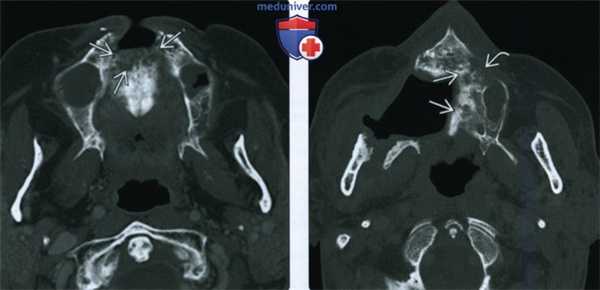

(Слева) При аксиальной КТ в костном окне у пациента, получавшего лучевую терапию по поводу плоскоклеточного рака носовой перегородки, визуализируется очаг литического характера в передних отделах верхней челюсти, представляющий собой треугольный участок деструкции костной ткани.

(Справа) При аксиальной КТ в костном окне у другого пациента определяются признаки выполненной резекции неба справа, а также изменения смешанного (склеротического и литического) характера в верхней челюсти слева, которая подвергалась облучению. Верхняя челюсть является относительно устойчивой к ионизирующему излучению, в ней редко возникает остеорадионекроз. Лучевые признаки идентичны таковым при поражении других костей лицевого скелета и основания черепа.